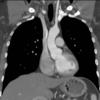

Nerves of the Thorax

Aquino et al Radiographics 2001;21:1275-1281

Images reproduced by permission of the publisher